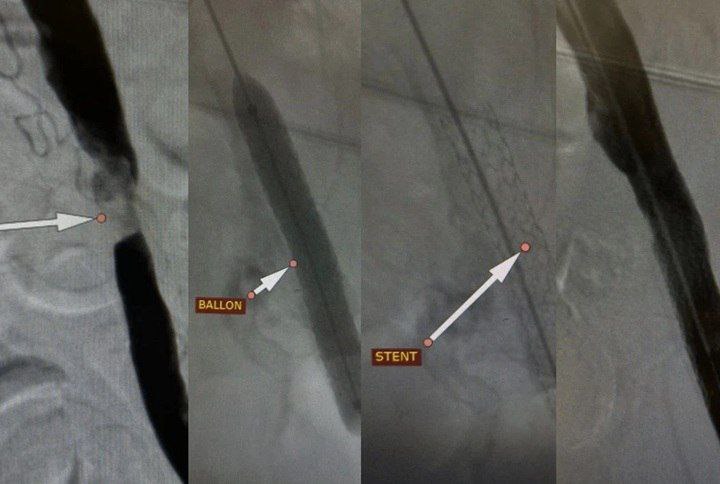

Однако сосудистые хирурги приняли решение о проведении щадящей эндоваскулярной операции. Через микропрокол, без разрезов, специалисты установили в сильно суженную артерию стент — тончайший металлический каркас, который расправил просвет сосуда и восстановил полноценный кровоток.